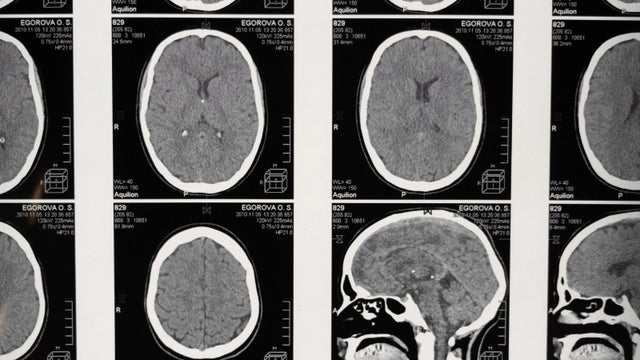

Técnicas de neuroimagem supõem um conjunto de processos que peritam o estudo correto do sistema nervoso. Eles são especialmente úteis para identificar lesões cerebrais em várias patologias, permitindo planos de intervenção mais precisos e detalhados para relacionar os danos ao déficit funcional que o paciente apresenta no dia a dia. O conhecimento e o gerenciamento deles são necessários para todos os profissionais que realizam seu trabalho no campo da saúde, mas também está no contexto da pesquisa em neurociência. O curso em técnicas de neuroimagem permite que você conheça essas técnicas e sua aplicação. Graças à sua metodologia on -line e ao monitoramento personalizado do ensino, você receberá um treinamento e treinamento de qualidade.

O curso em técnicas de neuroimagem prepara você para adquirir conhecimento relacionado às principais técnicas usadas no estudo do sistema nervoso, tanto no nível da estrutura quanto da função. Além disso, aprofunda as bases neurofisiológicas do comportamento humano, diretamente relacionadas ao estudo clínico do paciente neurológico, que tem afetação cognitiva devido a danos cerebrais.

O curso em técnicas de neuroimagem é dedicado a todos os profissionais que pretendem desenvolver sua atividade de trabalho em relação ao mundo da neurociência clínica, buscando realizar locais e interpretações corretas das alterações nervosas que permitem a capacidade da estrutura se relacionar com o processo cognitivo afetado no paciente.